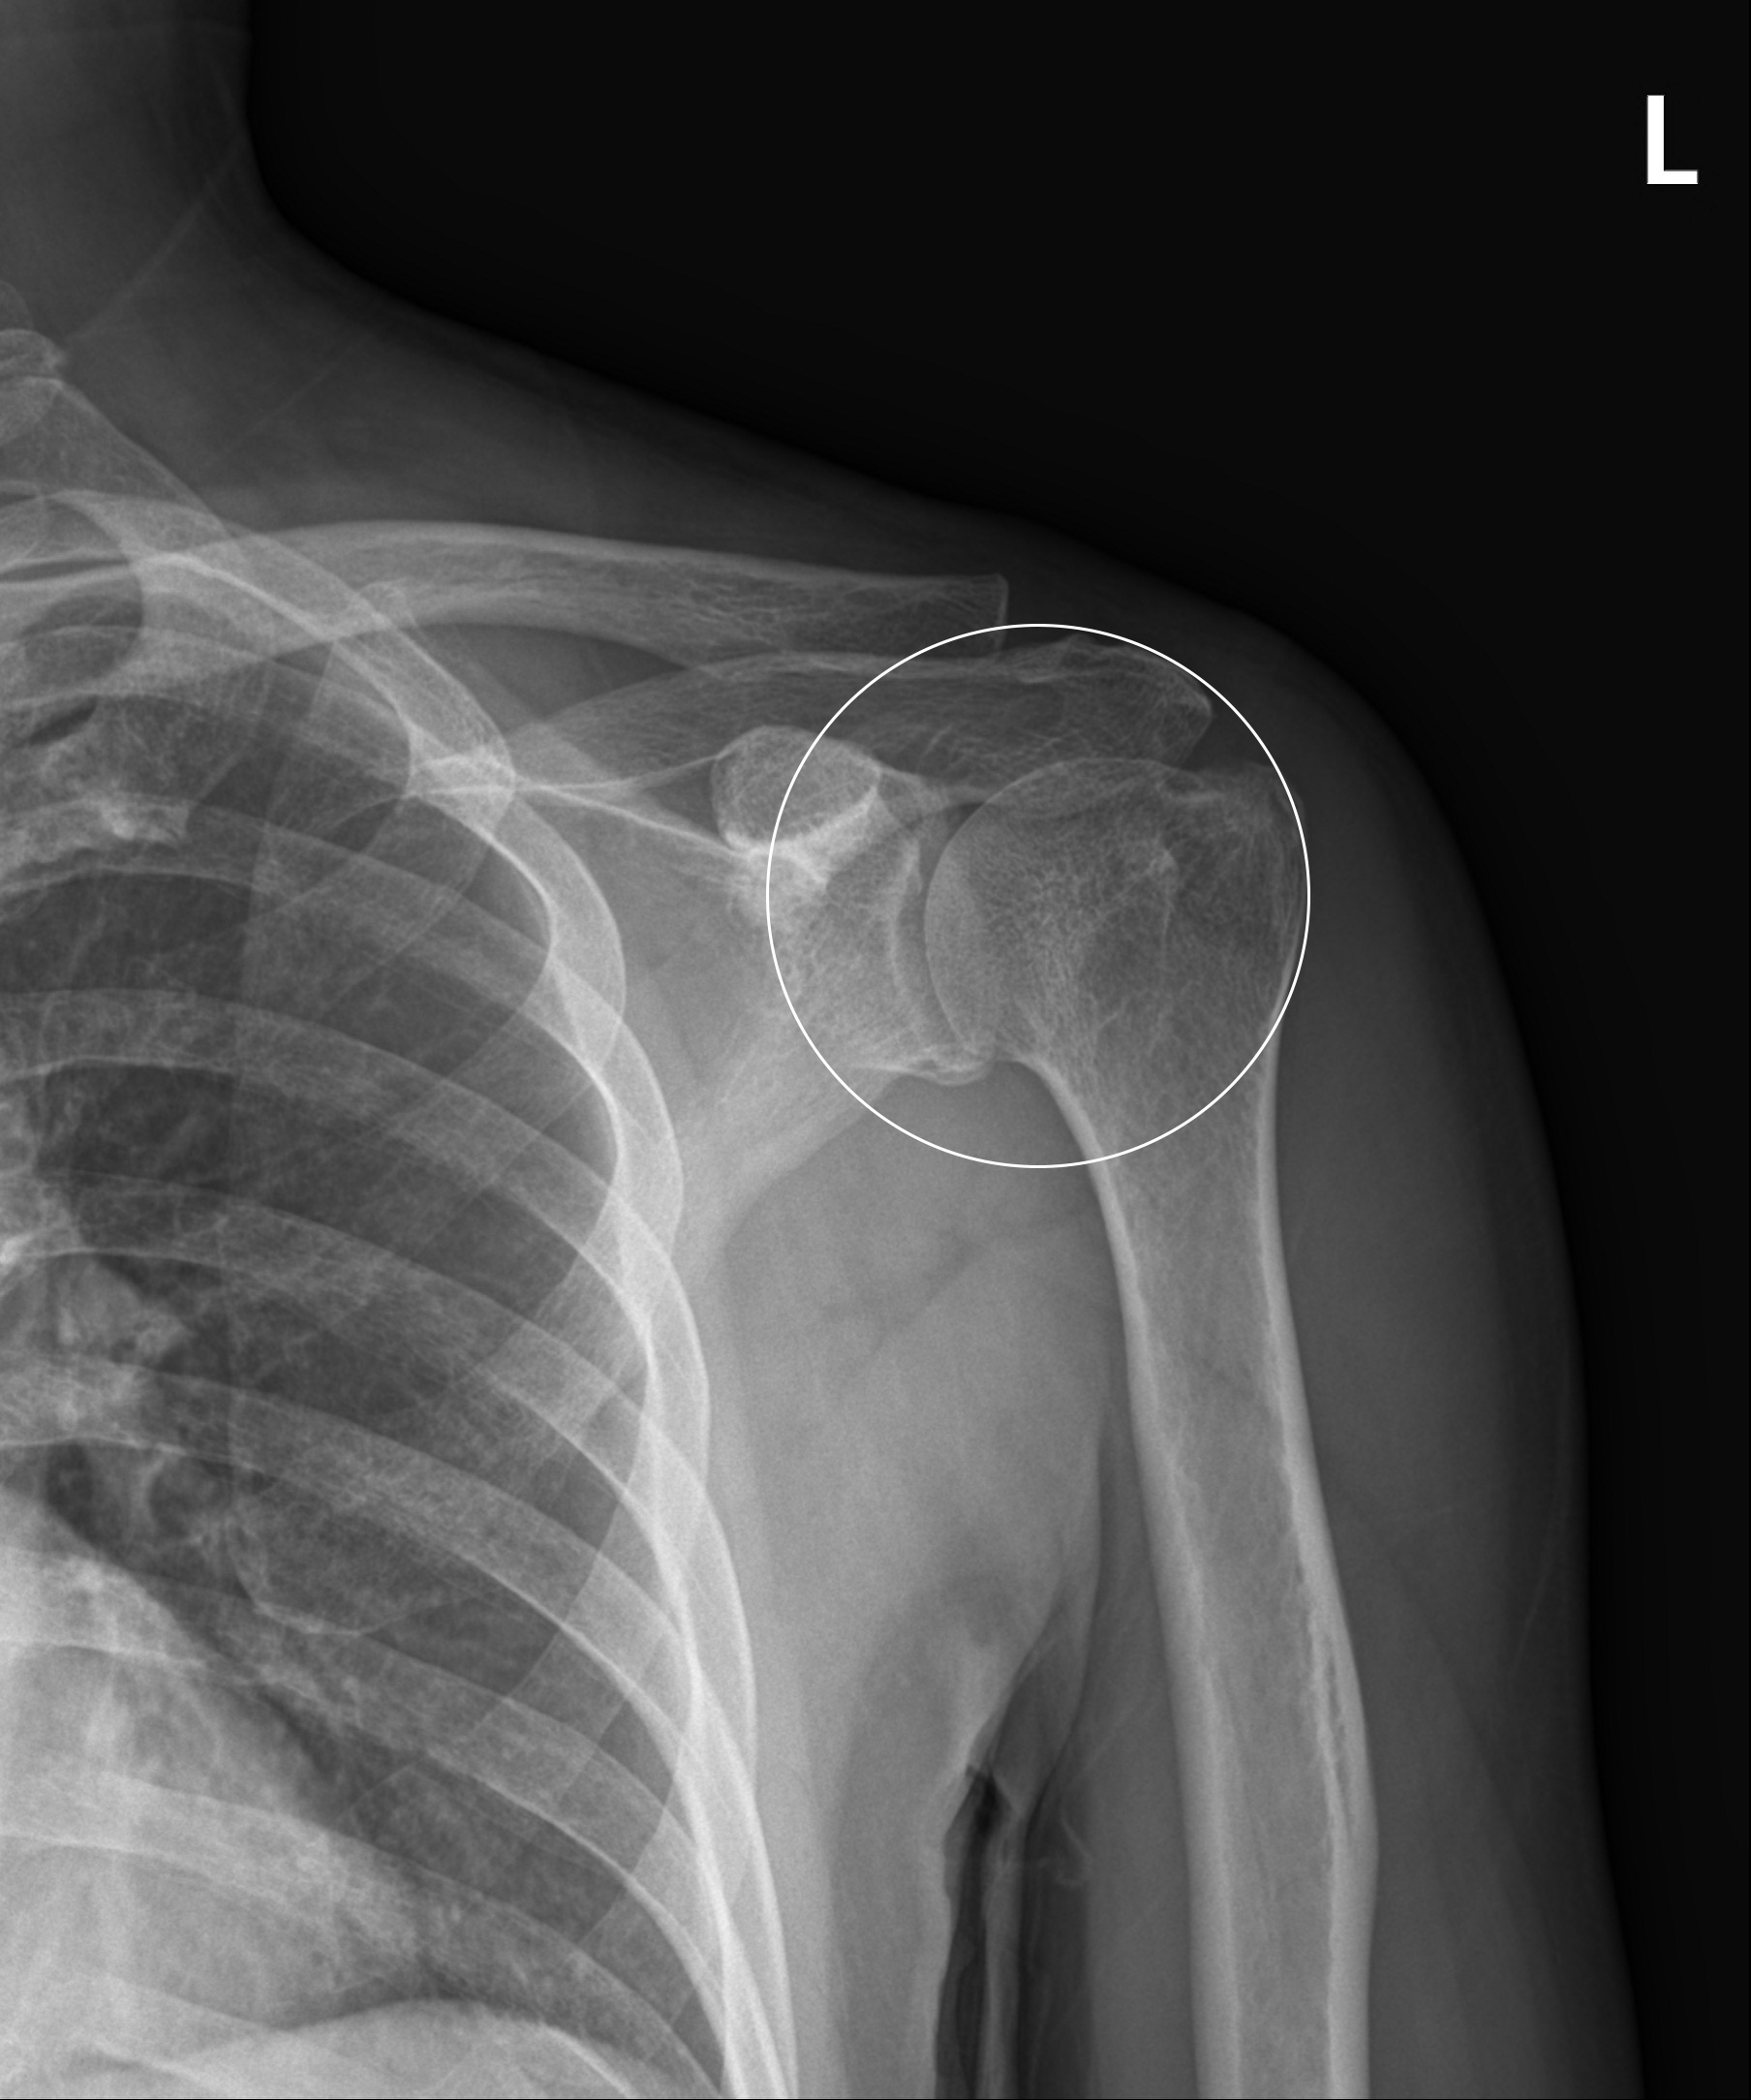

어깨충돌증후군

어깨 견봉과 위팔뼈인 대결절부 사이의 공간이 좁아지면서 뼈와 힘줄 사이에 마찰이 발생하는 질환을 말합니다. 정상 어깨관절에서는 이 공간이 충분하나 어깨를 많이 사용하거나 운동을 무리하게 한 경우 또는 퇴행성 변화 및 뼈의 변형으로 인해 견봉과 어깨 힘줄 사이에 간격이 줄어들어 마찰이 발생하고 힘줄 변성 및 통증이 발생하게 됩니다.

관절내시경을 이용한

견봉성형술 및 회전근개 변연절제술

2023-01-11

ㆍ환자 동의를 받은 자료이며, 이미지 사진은 실물과 다를 수 있습니다.